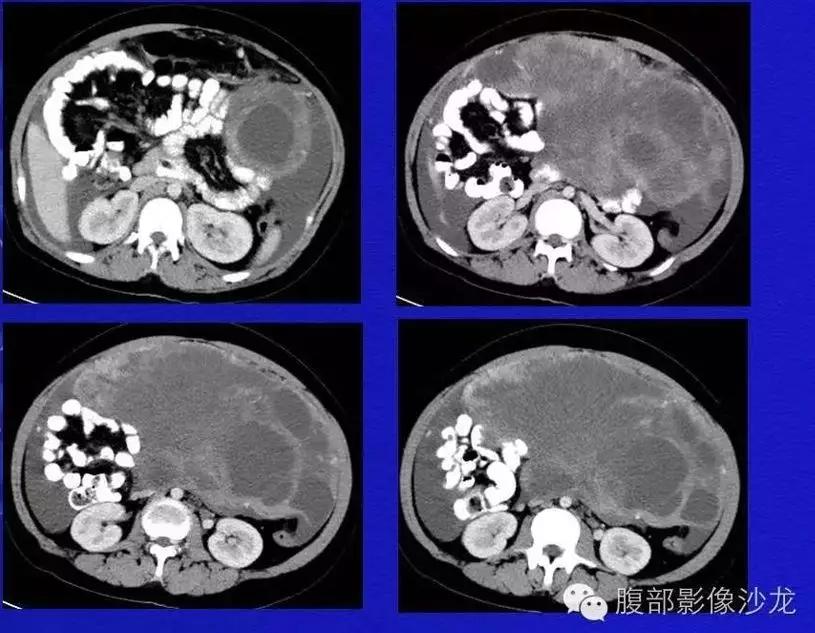

病理:子宫肌瘤粘液样变性

病例4 女,32岁,以“月经量增多伴经期延长半年。”

缘于患者入院前半年无明显诱因出现月经量增多,卫生巾由原来3包余增至5包不等,伴血块,经期由原来7天延长至10-15天不等,无痛经,无月经周期改变,无阴道异常排液,无畏冷、发热,无头晕、乏力等不适,未重视,未诊治。期间症状持续。2月前就诊我院,查彩超示:“子宫体大小约5.7*5.3*4.6cm,内膜厚约0.6cm,回声不均,左卵巢旁探及大小约4.2*3.5cm低回声区。”建议治疗,患者及家属表示考虑。期间症状持续,今就诊我科门诊,要求住院手术治疗,无腹痛等不适,门诊拟“卵巢囊肿”收住入院。既往史:2007年剖宫产一次,术顺。月经史:15 7/25 lmp2018.05.14,量中,无痛经。婚育史:已婚,1-0-3-1,末孕2007年剖宫产娩一男婴,儿子及丈夫体健。个人史、家族史均无特殊。

CA125 335.5(U/mL);2018-05-30 彩超:子宫宫体大小约5.6㎝×6.3㎝×4.9㎝,形态正常,宫壁回声欠均,内膜厚约1.8cm,回声不均。CDFI:子宫内未见明显异常彩色血流信号。左附件区探及一混合回声团块,大小约9.8㎝×7.9㎝,CDFI:其实性部分可见少许彩色血流信号。右附件区未见明显包块回声。

病理:卵巢子宫内膜样癌